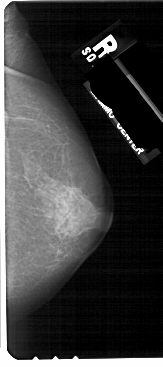

A_1373_1.LEFT_CC

RIGHT_CC LINES 5491 PIXELS_PER_LINE 2431 BITS_PER_PIXEL 12 RESOLUTION 43.5 NON_OVERLAY